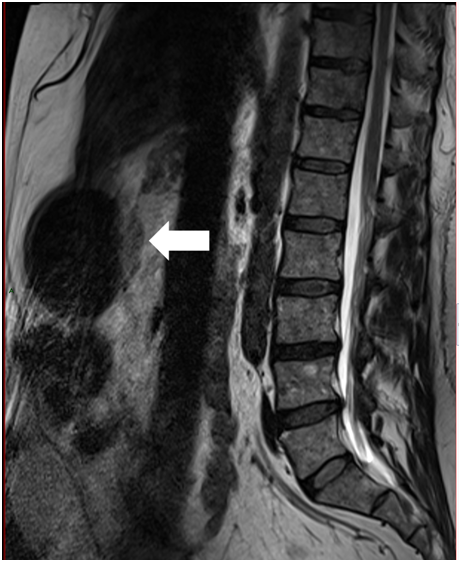

The patient consulted with a cardiology team where an electrocardiogram and an exercise test were performed, being reported normal. He was then referred to the orthopedics service due to shoulder pain persistence. A shoulder x-ray showed a tumor in the left thorax measuring 78.99mm in diameter (Figure 1). In follow up studies, a left humeral lesion of neoplastic appearance was revealed. In the magnetic resonance an intramedullary lesion is reported in the sternum, incidentally, a solid mass is observed in the left lung, it also shows tendinitis of the rotator cuff and subacromial impingement (Figures 2-4). Therefore, it is decided to perform a Computed Tomography scan which reported atelectasis mainly in the left upper lobe and a tumor measuring 65mm (Figure 5). The Positron Emission Tomography - Computed Tomography scan result was an increase of the metabolism by neoplastic activity, lymphadenopathy and bone lesions, hepatosplenomegaly and non- specific alterations in the colon (Figure 6).

Figure 2 Magnetic resonance with intramedullary lesion in the sternum.

Figure 3 Magnetic resonance with a solid mass observed in the left lung.

Figure 4 Magnetic resonance shows a left humeral lesion of neoplastic appearance.